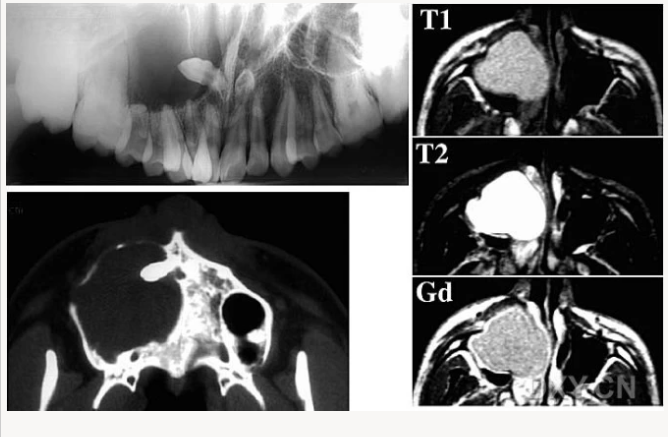

腺淋巴瘤[沃辛瘤

脂肪瘤